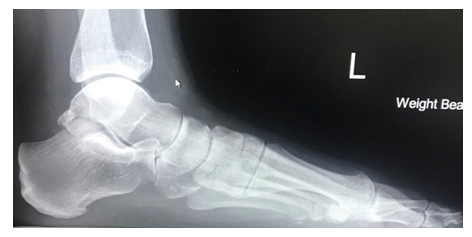

The X-ray above shows loss of alignment across the midfoot joints, irregular joint surfaces as a result of multiple fractures.

The X-ray to the left demonstrates well aligned midfoot joints with no signs of arthritis